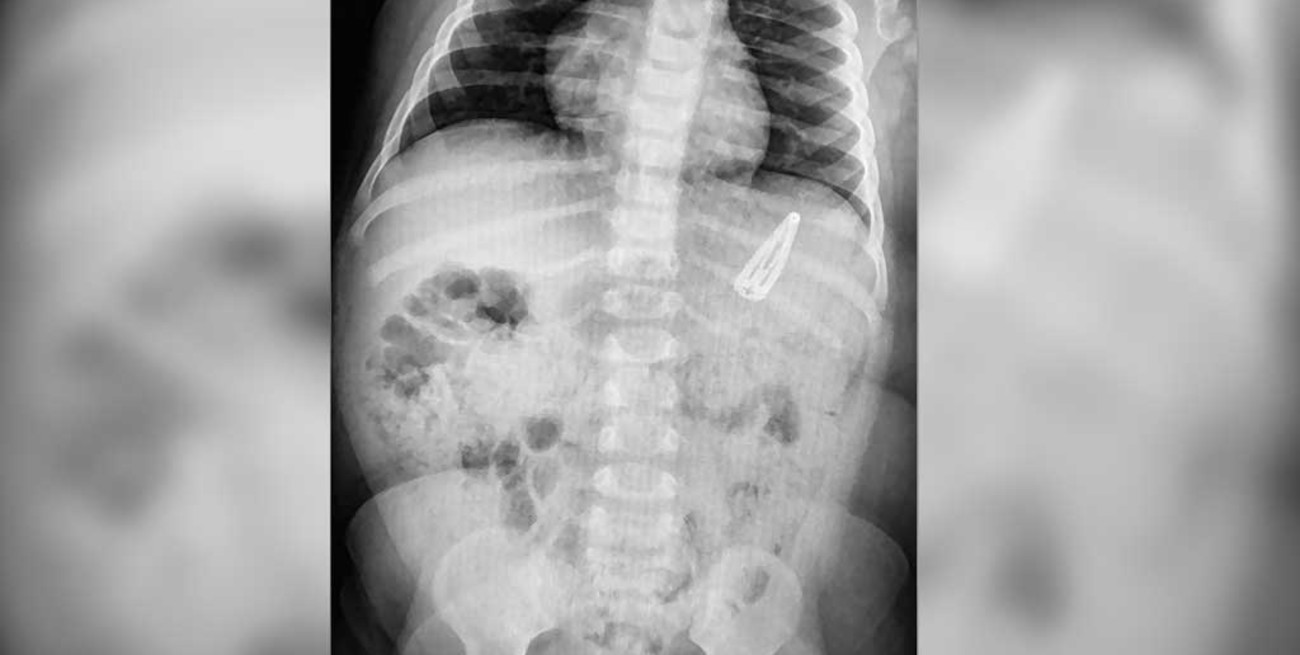

La radiografía está fechada dos horas después, y allí se ve bien que el clip está en el estómago. Con la punta, roma, hacia arriba, y la base hacia abajo, y afilados los bordes metálicos. Fácil era imaginarse que le sería difícil, al clip, salir de allí. Al menos sin dañarle a la nena las delicadas estructuras internas. No obstante, la propuesta fue esperar, y observar.